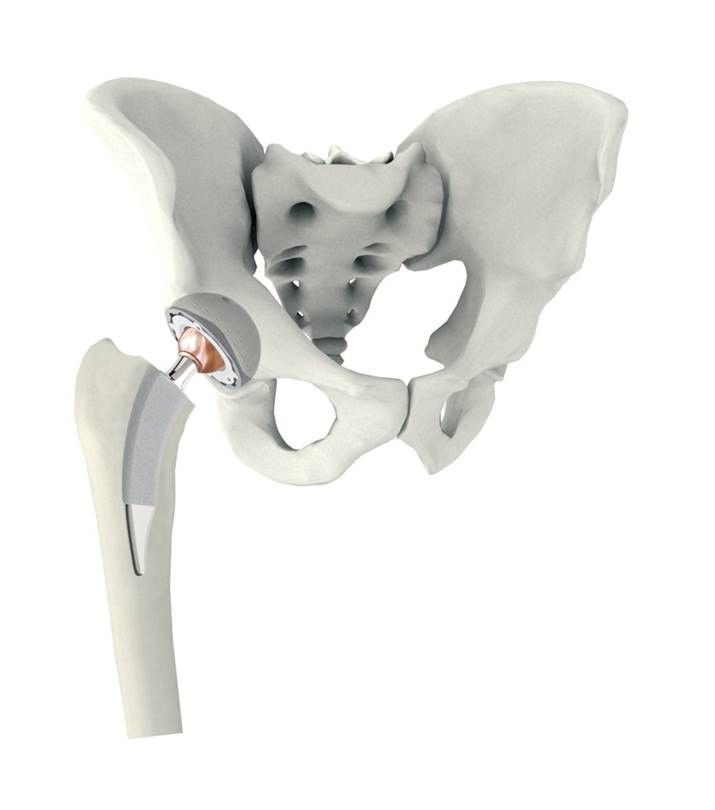

Aufbau eines künstlichen Hüftgelenkes

Das künstliche Hüftgelenk besteht aus vier Komponenten. Im Becken erfolgt die Implantation einer Pfannenkomponente, meist zementfrei, als Pressfit- oder Schraubimplantat. In dieser Titanpfanne wird ein sogenanntes Inlay aus hochverdichtetem Kunststoff verklemmt.

Im Bereich des Oberschenkels wird eine Schaftkomponente zementfrei (aus Titan) oder zementiert (aus einer Kobalt/Chrom Legierung) implantiert. Am oberen Ende befindet sich ein sogenannter Steckkonus auf den der künstliche Hüftkopf (Metall/Keramik/Oxinium) aufgebracht wird. Eine Komponente wird dann zementiert, wenn eine erheblich geminderte Knochendichte oder Osteoporose vorliegt.